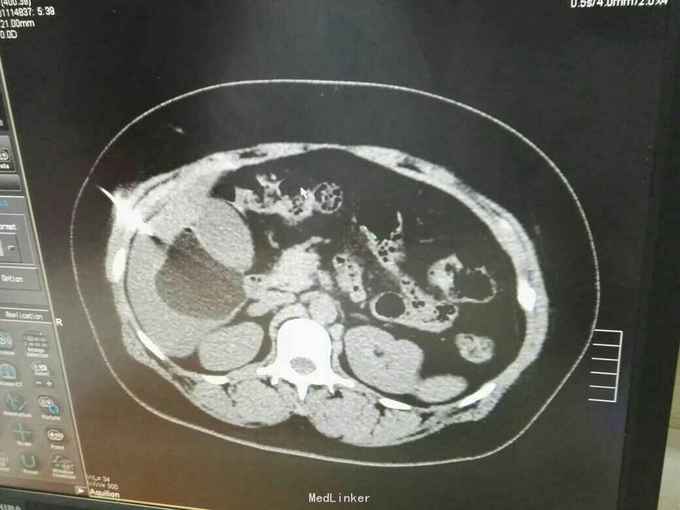

巨大肝囊肿

发现肝脏占位10年

肋弓下可触及囊性占位

肝囊肿

今日在局麻下行囊肿穿刺抽吸+无水酒精注射术 术中共抽取淡黄色液250ml